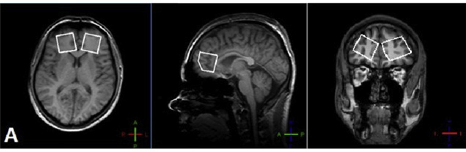

Fig. 1 1H MRS VOI localizations.

1H MRS (MEGA-PRESS pulse sequence [Mescher, NMR Biomed 1998;11:266]) was used for GABA and GLX detection. Volumes of interest in size of 30 × 30 × 30 mm were placed in the left and right frontal lobes in the areas of the anterior cingulate cortex (ACC) (Fig. 1).

Fig. 1 1H MRS VOI localizations.

Fig. 1 1H MRS VOI localizations.